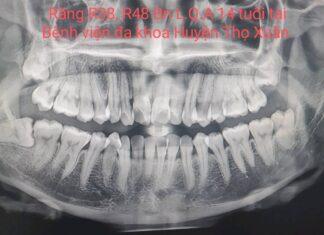

NHỔ RĂNG KHÔN MỌC LỆCH AN TOÀN-KHÔNG ĐAU TẠI BỆNH VIỆN ĐA KHOA HUYỆN THỌ XUÂN.

**Răng khôn hay còn gọi là răng số 8 hay răng cối lớn thứ 3, là răng mọc cuối cùng của hàm. Răng thường...